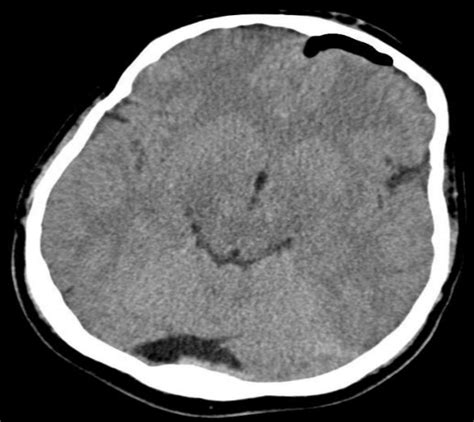

Diagnosis: How Doctors Find the Air

So, you’re experiencing some weird symptoms, and your doctor suspects pneumocephalus . How do they actually figure out if there’s air in your head? Well, it’s usually a combination of a thorough medical history, a physical examination, and most importantly, medical imaging. The doctor will ask about any recent head injuries, surgeries, or medical procedures you’ve undergone. They’ll also perform a neurological exam to check your reflexes, coordination, strength, and mental status. The real stars of the show, though, are the imaging techniques. Computed Tomography (CT) scan of the head is the gold standard for diagnosing pneumocephalus. CT scans are excellent at visualizing bone and detecting air, which appears as very dark areas on the scan. Doctors can clearly see the location and amount of air within the cranial cavity. They often look for a characteristic